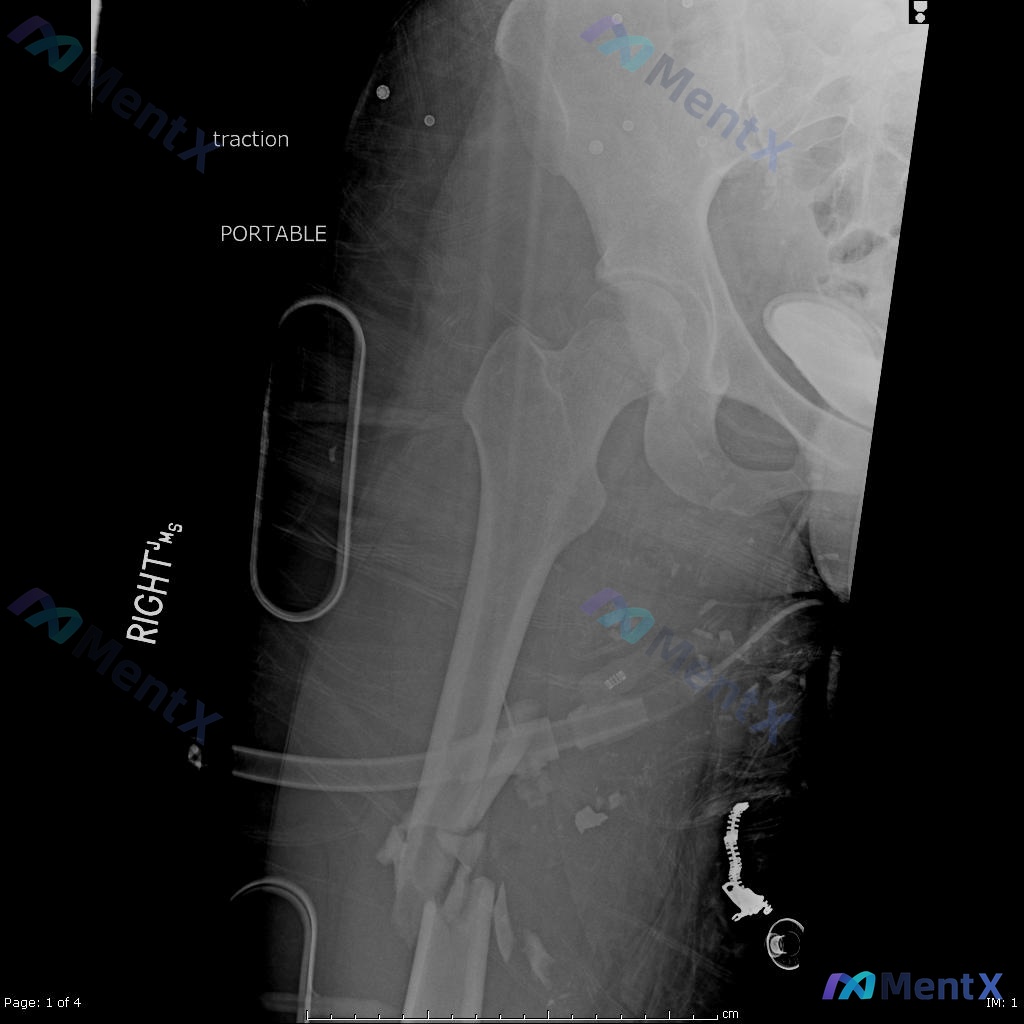

看到一个挺有代表性的创伤骨科病例,结合影像和临床分析整理了一下思路,关于「髓内钉固定术后负重时机」的误区其实还挺普遍的。 --- 一、先把病例核心信息捋清楚 基本情况:22岁男性,高能量车祸受伤 影像关键所见: - 术前(图A/B):右侧股骨干中段粉碎性骨折,多块游离骨块,移位明显;局部软组织肿胀;...